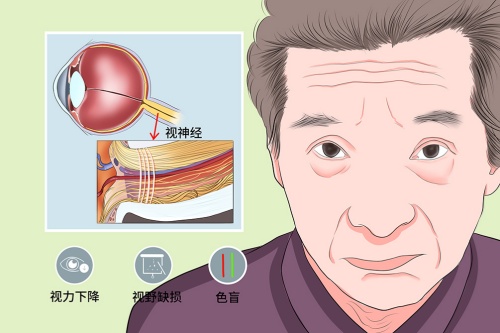

青光眼专科:疑难病例的"克星"

钟晓东医师在青光眼的诊断及手术治疗方面颇有特色,特别擅长复杂性青光眼的个性化治疗,手术成功概率高,患者术后眼压控制稳定。洪斌副高医师则专注于难治性青光眼的综合治疗,尤其擅长青光眼引流阀植入术及联合手术,为晚期青光眼患者保留有用视力。

技术亮点:科室开展的Express微型引流器植入术,较传统手术眼压控制达标率提升30%;选择性激光小梁成形术(SLT)可减少患者长期用药依赖。